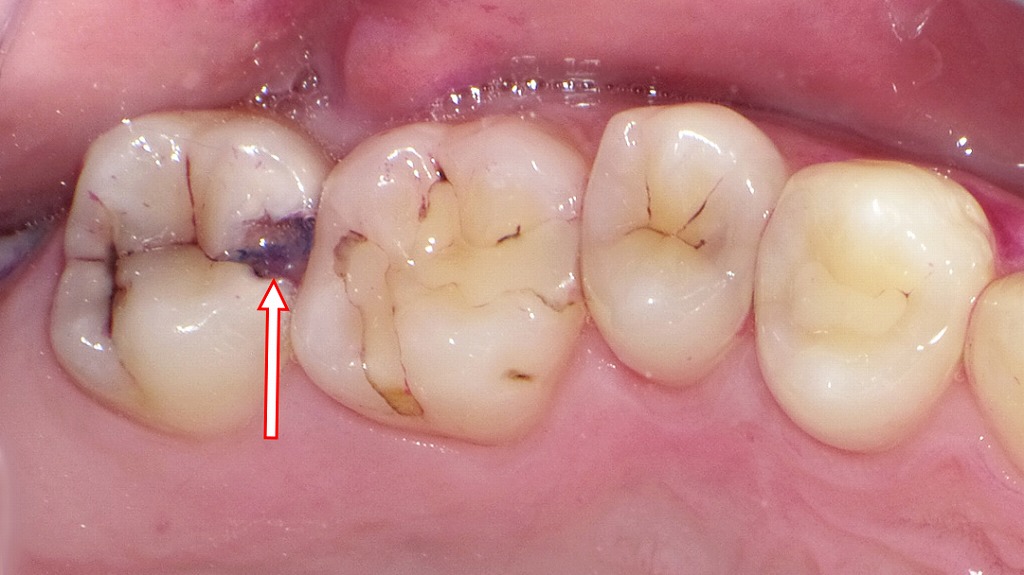

この画像は上顎右側第2大臼歯(7番)を中心に撮影された口腔内写真です。矢印の部分に注目すると、次のような所見が読み取れます。

上顎7番(矢印の歯)に黒褐色の変色部が見られます。これは**C2(象牙質まで進行した虫歯)**の典型的な所見です。

すでにエナメル質を越えて象牙質に達しており、冷たいものや甘いものにしみやすい段階です。 - 隣接面(6番との間):

食片(食べかす)が詰まりやすい形態になっており、**食片圧入(しょくへんあつにゅう)**が起きています。

これにより歯ぐきが炎症を起こしやすく、歯周ポケットや歯肉出血の原因にもなります。 - プラーク・磨き残し:

歯と歯の間、特に7番と6番の接触部付近に歯垢の付着が確認できます。

奥歯は歯ブラシが届きにくいため、フロスや歯間ブラシを使用しないと汚れが残りやすい部位です。 - 口臭との関連:

このような虫歯や磨き残し、食片圧入は細菌の繁殖源となり、口臭の原因にもなります。

とくに歯肉溝や虫歯内部にたまったプラークから揮発性硫黄化合物(VSC)が発生します。

- 虫歯治療:

C2段階のため、虫歯部分を除去し、コンポジットレジン充填またはインレー修復が必要です。 - 清掃指導:

歯間ブラシやデンタルフロスの使用方法を指導し、磨き残しの改善を図ります。 - 口臭対策:

原因歯の治療後、定期的な**歯石除去・クリーニング(PMTC)**を行うことで再発と口臭を防止できます。